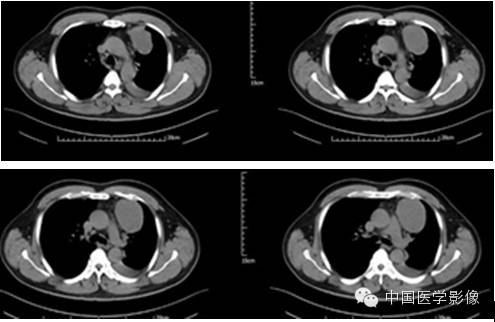

病例1【病史】

患者男,50岁。

患者因“突发胸痛4余天”入院。患者无发热、盗汗,无声音嘶哑,无咳痰,无面部及双下肢肿胀。门诊以“左前上纵膈肿瘤”收入院。患者自发病以来,饮食睡眠可,大小便正常,体重较前无明显减轻。既往高血压病史1年,否认其他传染病史。

专科查体:胸廓对称,双侧呼吸动度均等,胸壁无明显压痛及肿块,双侧语颤正常,双肺叩清音,左下肺呼吸音低,右肺呼吸音可,双肺未闻及干湿啰音。

入院诊断:左前上纵膈肿瘤:畸胎瘤?

【影像资料】

平扫

动脉期

静脉期

延迟期

【病理结果】

孤立性纤维性肿瘤